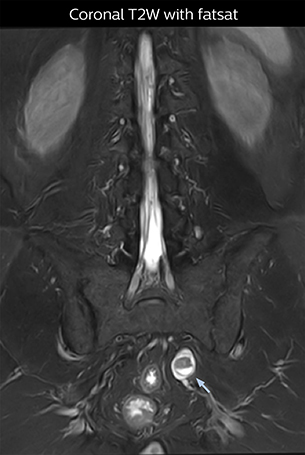

“The intra-luminal signal of veins, especially around the intervertebral space, can be suppressed well with NerveVIEW. As a result, we can easily observe the detailed nerve structure around the posterior ganglion,” he says. “This is why we use 3D NerveVIEW for intraforaminal stenosis and extraforaminal stenosis/herniation (lateral disc herniation). On the other hand, if herniation is suspected to exist inside the dorsal root ganglion (DRG), balanced TFE or ProSet-FFE is applied. NerveVIEW is not suitable for evaluating the median type of herniation.” The SE-EPI DWI-based method for MR neurography works well for large FOV exams like whole-body MRI, but focal examination of nerves is often limited by the attainable spatial resolution (both inplane and slice direction) and geometric distortion. “3D NerveVIEW achieves higher in-plane resolution – close to our other routine spine sequences – and the source images can be used instead of adding a fat-suppressed T2-weighted sequence,” Tanji says.

Implementing NerveVIEW without lengthening exam time “The source images of NerveVIEW exhibit a contrast similar to STIR or fat-suppressed T2-weighted images. So, in our neurography exams we are replacing the 2D T2-weighted coronal sequence with 3D NerveVIEW. With this, we add a lot of useful information without adding scan time. This is important for patients with severe lower extremity symptoms, as they often find it difficult to maintain still during the whole MRI examination, so the exam should be as short as possible.” “We have currently implemented 3D NerveVIEW on our Achieva 3.0T dStream MRI system only. Because the 3D NerveVIEW method is based on a background signal suppression technique, we decided to use the high SNR of our 3.0T MRI system for obtaining the best possible visualization of peripheral nerves,” says Tanji. “Where NerveVIEW of the lumbar plexus is currently used as a subroutine scan for patients with strong lower limb symptoms, its use for visualization of the brachial plexus, is currently limited to special cases such as schwannomas and neuritis, usually only 1 or 2 cases per month.”

“NerveVIEW can clearly show nerve courses and presence of nerve compression. However, when multiple abnormalities are seen, it can still be hard to determine which nerve is causing the symptoms,” says Dr. Yabuki. “In our experience so far, we see abnormal findings on NerveVIEW in about 70% of elderly patients. As the pain is usually caused by only one nerve, we thus need to find the exact corresponding nerve.” “With a nerve root block, the patient's pain is improved by infiltration of local anesthesia directly around the nerve root considered to be responsible. Knowing such nerve root block findings prior to image interpretation, helps to easily recognize abnormal findings on NerveVIEW as well. In other words, without a priori knowledge, based on symptoms and/or nerve root block findings, we must be aware of the possibility of overdiagnosis.”

The addition of the nerve-selective NerveVIEW sequence to its spine MRI protocol has given NFMC competitive advantages, according to Tanji. “Since we started including NerveVIEW routinely, the demand for lumbar spine MRI examinations has increased, especially for pre-surgical planning purposes and for patients with chronic lower extremity symptoms,” he says. “Moreover, because no other hospitals in our region are doing nerve plexus imaging yet, we often receive referrals for MR neurography studies from other hospitals even if they have an MRI scanner. Some requests come from as far as 100 km away. NerveVIEW definitely provides us a competitive advantage.” “Based on our experience, we can certainly recommend NerveVIEW to other centers,” Dr. Yabuki adds. “The sequence opens up many possibilities to facilitate the diagnosis of lower extremity pain and to inform our decision-making regarding therapy and surgery.”